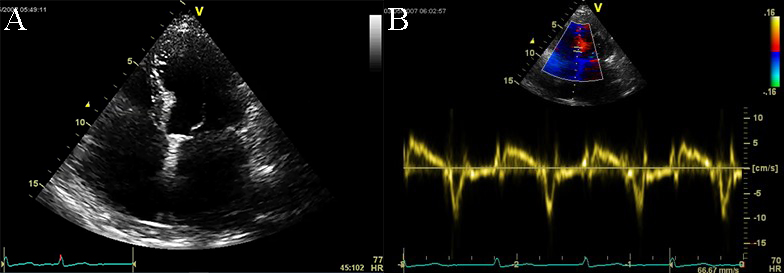

Doppler echocardiography and tissue Doppler imaging show diastolic dysfunction, frequently with a restrictive pattern. Different aspects of the diastolic function can be revealed, but usually more than grade 2 diastolic dysfunction, with increased filling pressures: an elevated peak mitral inflow velocity (high velocity of E wave), rapid early mitral inflow deceleration (low deceleration time). E/A ratio greater than 0.8, deceleration time of E wave lower than 200 milliseconds, and frequently lower than 160 milliseconds, E/e’ ratio with a value above 9, are features found in the echocardiographic examination of RCM (see Fig. 10 and Appendix Video 5) [1, 4].

Fig. 10.Echocardiographic aspect of RCM. (A) Apical 4c view of an

elderly patient with idiopathic restrictive cardiomyopathy, severe biatrial

enlargement (left atrium